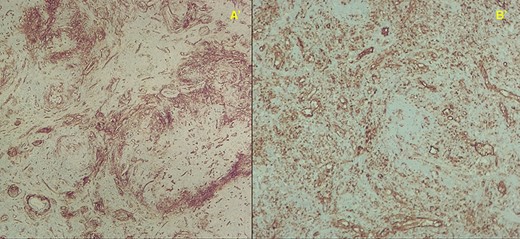

Immunohistochemistry stainings showing abundant capillaries; A′—CD34+ 40X and B′—CD31+ 100X magnification, respectively.

Histopathology examination confirmed the presence of areas of sclerosis, with scarring tissue surrounded by abundant vascular spaces (Fig. 4). The immunohistochemical evaluation revealed clusters of differentiation CD31+, CD34+ and CD8—cells consistent with SANT (Fig. 5).

Immunohistochemistry staining of SANT can present itself as three different patterns, including endothelial-cell lining CD34−, CD31+, CD8−; capillary-like CD34+, CD31+,CD8− staining (consistent with our patient’s report), and a venous CD34−, CD31+, CD8− immunophenotype, which indicates the derivation from sinusoidal capillary and vein-like elements [2, 6, 5].